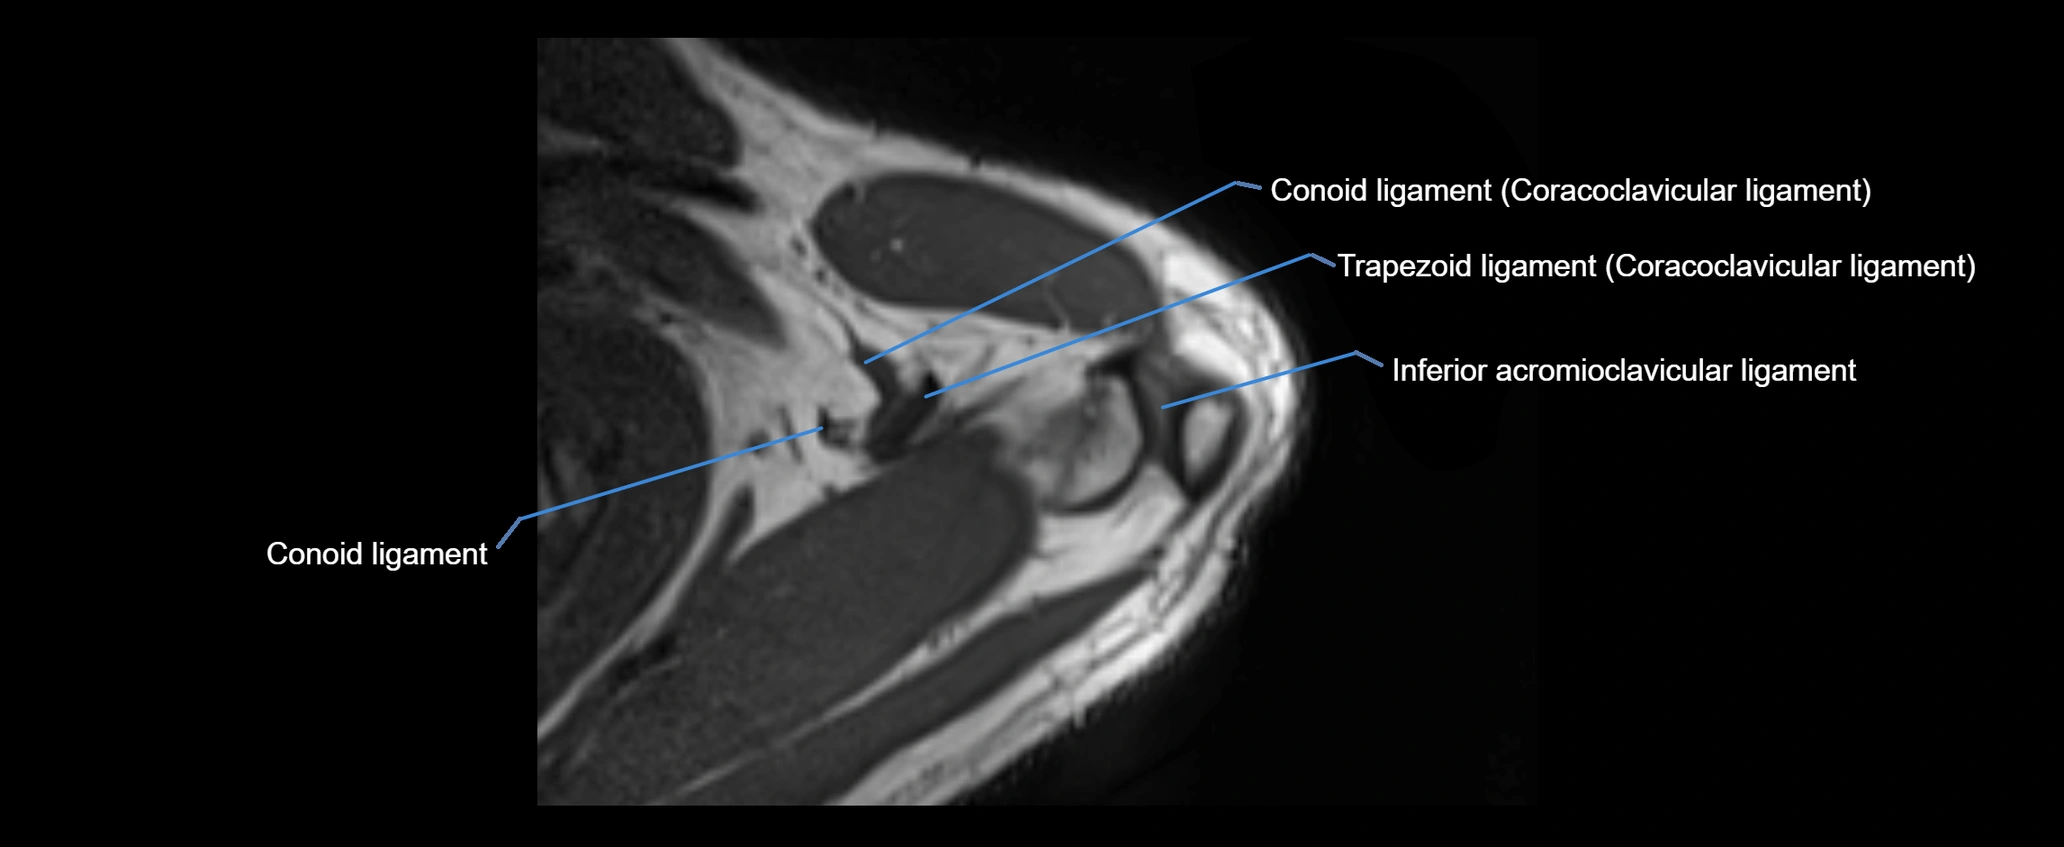

MRI images

image

MRI Appearance

• Proton Density Fat-Saturated (PD FS):

• Normal ligament: Low signal, uniform thickness.

• Partial tear or sprain: Bright signal or contour irregularity.

• Complete tear: Clear discontinuity with bright signal gap and joint effusion.

• Excellent for assessing joint capsule, coracoclavicular ligaments, and periarticular edema.